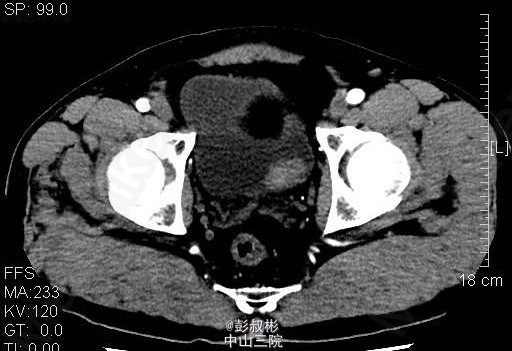

男性,54岁,血尿1月余。盆腔CT:膀胱左侧壁肿块,约27×23mm,考虑膀胱癌可能性大。患者家属要求保留膀胱,中腹部CT平扫+增强扫描+CTU,结合CTU:膀胱左侧可见一充盈缺损影,大小约34×25mm,双侧肾盂肾盏未见扩张,其内未见异常密度影,双侧输尿管通畅,未见增宽或狭窄。双肾大小、形态未见异常,双肾可见多发低密度影,CT值-15~15HU,最大约14×13mm,增强扫描强化不明显。双侧肾上腺大小、形态未见异常,其内未见异常密度影,增强扫描未见异常强化。膀胱充盈良好,膀胱左后壁可见一类圆形肿块向腔内突出,大小约34×25mm,增强扫描可见明显强化。前列腺不大,其内未见异常密度影。胆囊体积不大,囊壁增厚,可强化,其内未见异常密度影。片内所见肝实质密度普遍性减低,CT值约48HU,低于同层面脾实质CT值。